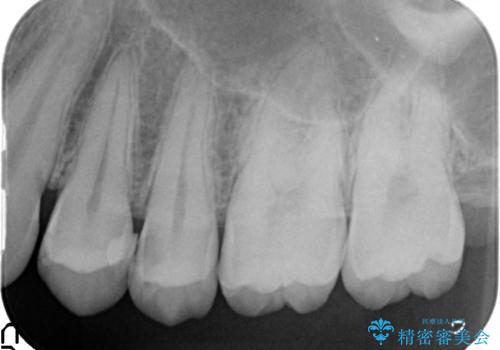

X線撮影によりわかる、内在する虫歯治療

X線検査により、歯の変色部は大きな虫歯が内在することがわかりました。